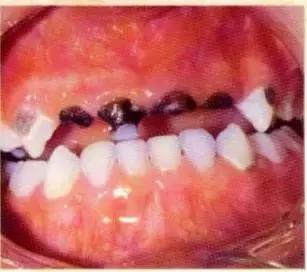

来自一位5岁孩子的口腔图

这只是噩梦的开始。

这样的牙齿还会引发更严重的牙齿问题。